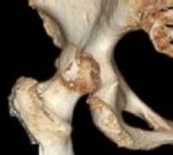

A 22-year-old rugby player has a history of recurrent anterior shoulder instability. A 3D reconstructed pre-operative CT scan is shown. The imaging demonstrates an inverted pear-shaped glenoid with a calculated anterior-inferior bone loss of 27%. What is the most appropriate surgical management to minimize his recurrence risk?

Correct Answer: Latarjet procedure (coracoid transfer)

Explanation:

In patients with anterior shoulder instability and significant glenoid bone loss (>20-25%, often creating an 'inverted pear' appearance), soft tissue procedures alone (like an arthroscopic Bankart repair) have unacceptably high recurrence rates. A bony augmentation procedure, most commonly the Latarjet procedure (transfer of the coracoid process with the attached conjoint tendon to the anterior glenoid neck), is the gold standard treatment.